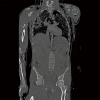

Figure 1

Computed tomography scan during initial assessment of the patient at the emergency department, in this coronal plane revealing subcutaneous emphysema, left sided pneumothorax and pneumomediastinum. Furthermore, a suggestion of a rupture of the left main bronchus can be seen.